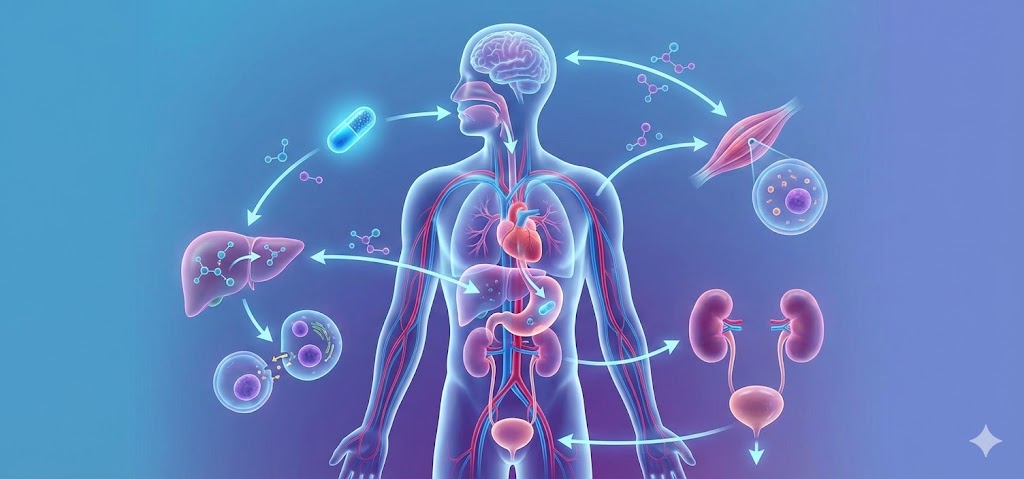

Danışana yüksek kalite hizmet vermek için hem yüz yüze hem de interaktif eğitimlerin gerçekleştirildiği paketlerle, eczanenizi günümüz dünyasında proflaksi, tedavi ve tedavi sonrası hasta-danışanın vazgeçmeksizin güvenle geleceği bir noktaya taşımak mümkün. Daha detaylı bilgi almak için lütfen iletişime geçiniz.